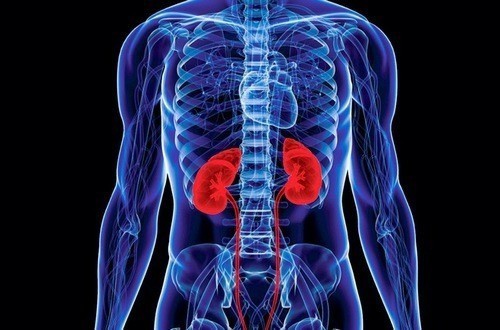

Thận là cơ quan quan trọng, có chức năng chính là lọc chất thải từ máu và duy trì sự cân bằng dịch tối ưu trong cơ thể. Nằm ở mặt sau của thành bụng, hai bên cột sống, thận giúp đảm bảo các hệ thống trong cơ thể duy trì trạng thái ổn định và cân bằng nội môi để hoạt động bình thường.